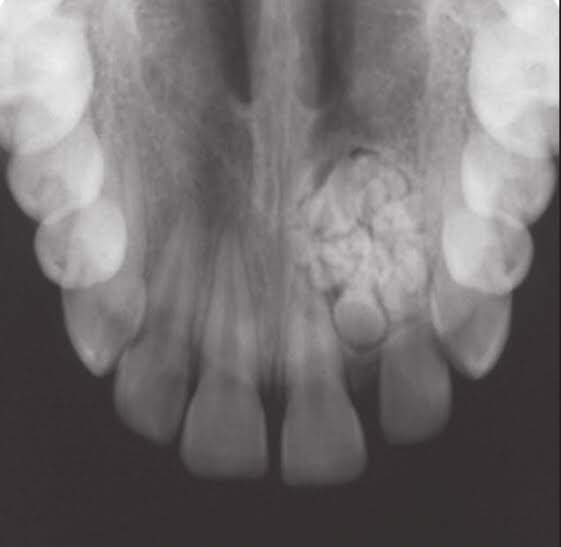

2. Compound Odontoma:

• Location: Anterior maxilla (62% – unerupted canine)

• Collection of small radio-opaque masses, some/all may be tooth like structures “denticles“

• Formed by exuberant growth of dental lamina or proliferation of enamel organ

• Radiographically, cluster of multiple tiny toothlike structure within a fine radiolucent rim.